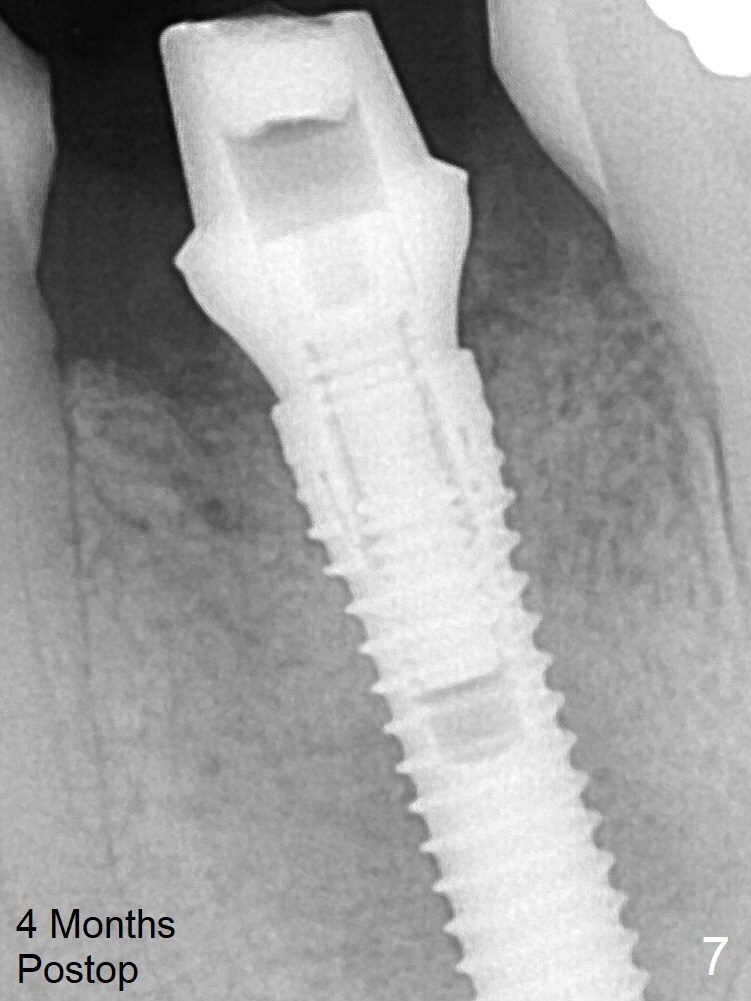

It appears that a 3.8x18 mm  implant is not placed deep enough.  Following 3-4 more turns of the implant and placement of a 5.5x4(3) mm abutment (Fig.5 A), allograft is placed (*).  The bone around the implant appears to have regenerated 4 months postop (Fig.7).